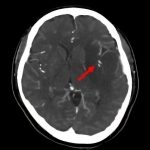

断層撮影

手術前1